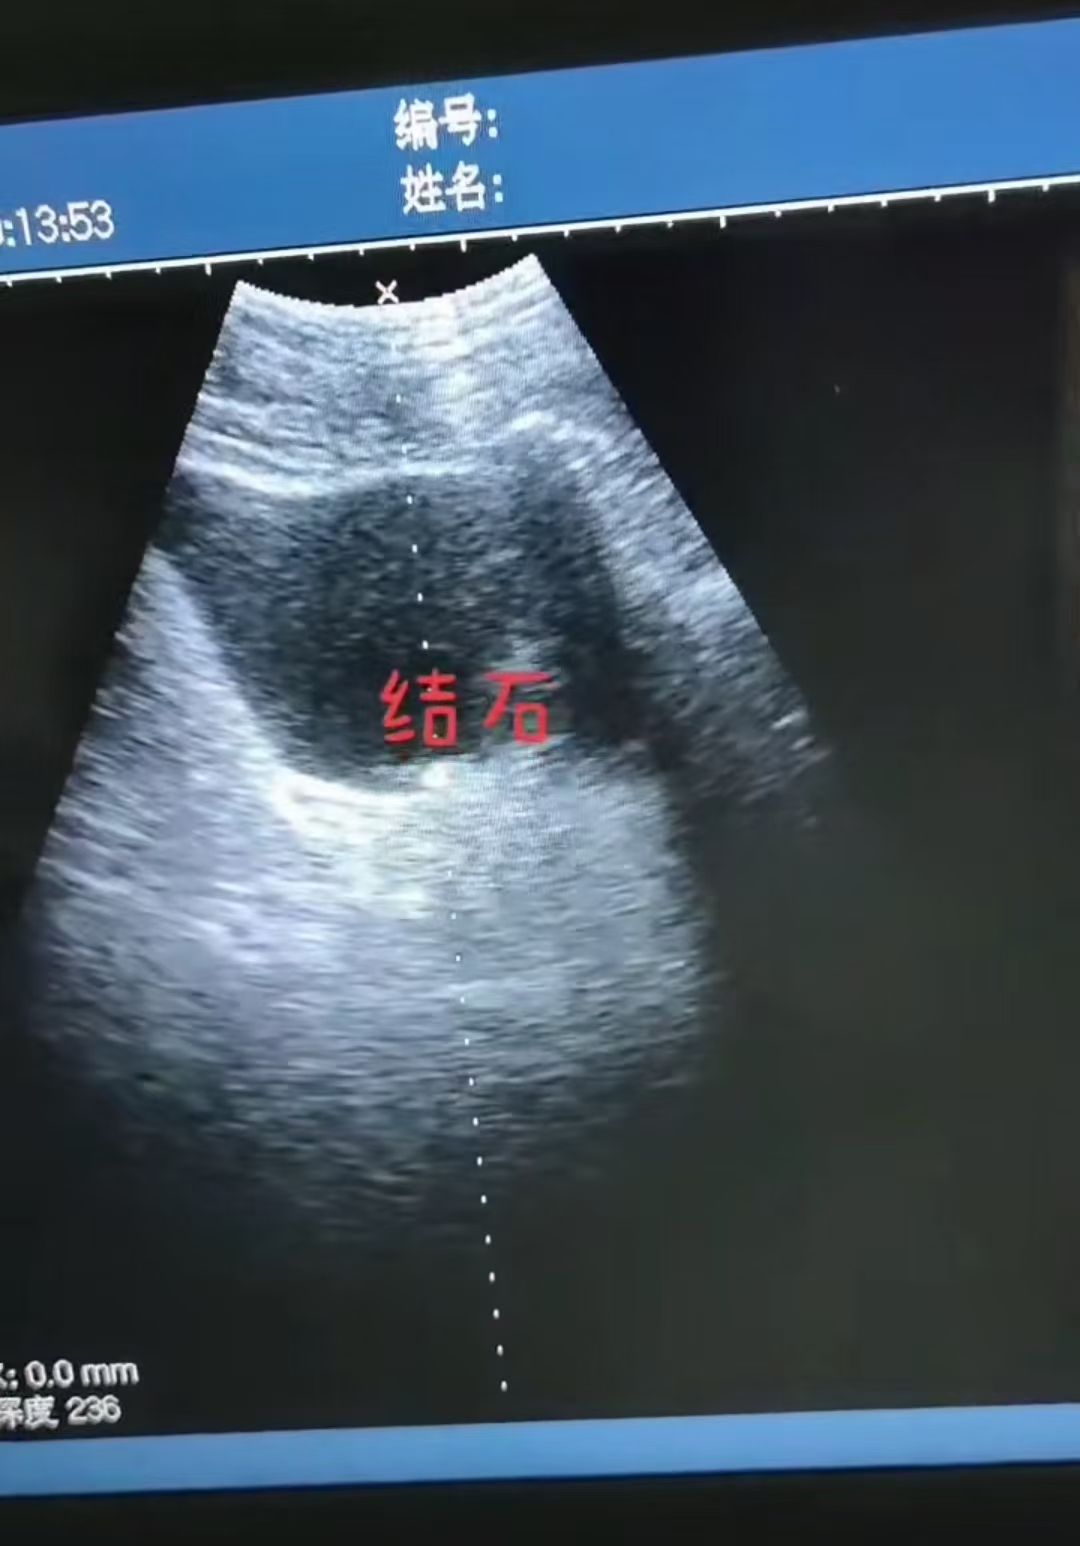

肾结石B超检查是通过超声波成像技术观察肾脏结构,识别结石的位置、大小及是否伴有肾积水等并发症。检查时,医生会将探头放置在腰部或腹部,通过声波反射形成的图像判断结石特征,如强回声光团、后方声影等。 一、检查前的准备 1、无需空腹:肾结石B超通常不需要空腹,但若需同时检查输尿管或膀胱,可能需要提前憋尿。 2、体位调整:检查时需平躺或侧卧,暴露腰腹部,方便探头移动。 二、B超图像中的肾结石特征 1、强回声光团:结石在B超中表现为明亮的白色或高亮区域(强回声),与周围组织形成明显对比。 2、后方声影:结石会阻挡超声波传播,在光团后方形成黑色无回声区域(声影),这是结石的典型标志。 3、伴随表现:若结石引起尿路梗阻,可能显示肾盂扩张或肾积水(肾脏内出现液性暗区)。 三、B超检查的局限性 1、小结石可能漏诊:小于3毫米的结石可能因体积过小或位置隐蔽而难以发现。 2、肠道气体干扰:肠道积气可能遮挡部分肾脏区域,影响观察。 3、结石成分无法判断:B超无法区分结石类型(如尿酸结石、草酸钙结石)。 四、检查结果解读要点 1、结石位置:明确位于肾盂、肾盏或输尿管连接处。 2、结石数量:单发或多发,影响后续治疗选择。 3、并发症评估:如肾积水程度(轻度、中度、重度)及肾功能是否受损。 五、与其他检查的对比 1、CT检查:更精准,可发现更小的结石,并判断成分,但辐射量较高。 2、X线检查:仅能显示含钙结石,对尿酸结石不敏感。 3、尿液分析:辅助判断结石成因(如尿酸水平、感染等)。 六、后续建议 1、复查随访:小结石可通过多饮水、药物排石,需定期复查B超监测位置变化。 2、结合症状判断:若B超阴性但腰痛、血尿明显,需进一步做CT或尿路造影。 3、调整饮食(如减少高草酸、高嘌呤食物)。 总结:B超是肾结石筛查的首选方法,具有无创、快捷的优点,但需结合临床和其他检查综合判断。检查后应遵医嘱选择治疗或随访方案。 即刻关注凯信微信号xzkxele,就能查看更多关于B超机、彩超机、兽用B超、宠物彩超的详情。(只需在公众号里搜“凯信超声”或扫描下方的二维码就可以加关注!)如需咨询报价信息,可联系客服热线15050003098 400-928-6626. |